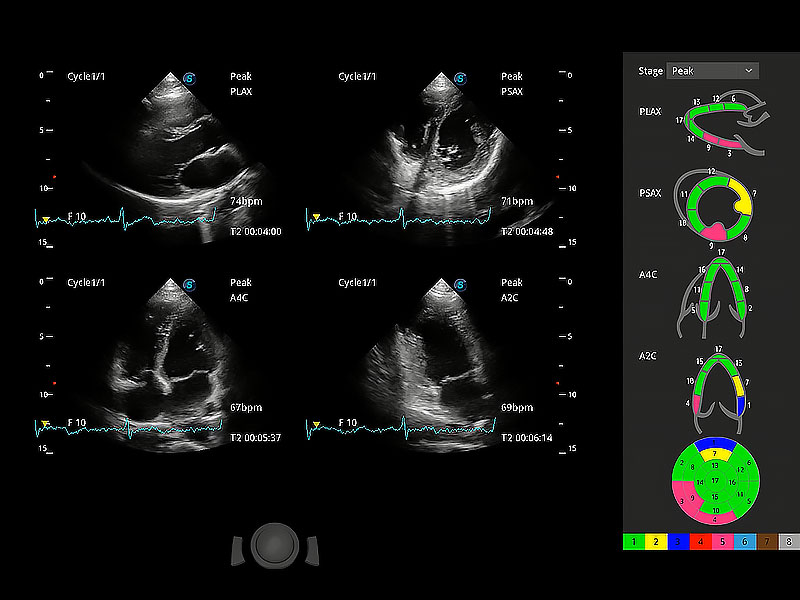

具備多種協(xié)議可選,同時支持17階段劃分法和專業(yè)的SE報告。